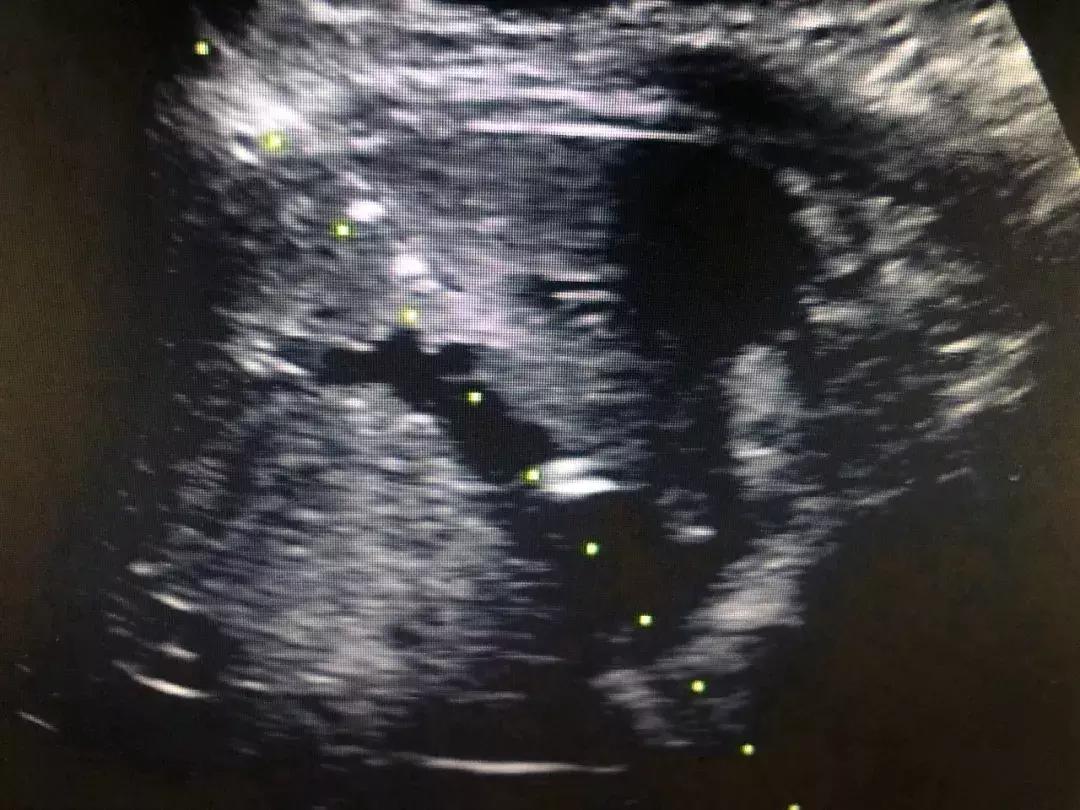

近日,一位75岁的胰头癌伴肝内转移的患者,肝内胆管明显扩张,肝功能差,黄疸指数高,无法行根治切除术,纠结的患者家属找到了西安市中心医院超声科,通过充分的术前评估,郑瑜主任等为其进行了超声引导下经皮肝穿刺胆管引流术(PTCD),随着大量的胆汁的流出,患者状态明显改善,各项指标趋于平稳。

超声引导下PTCD是在超声监测下,利用特殊穿刺针经皮穿入肝内胆管,再将外引流管置入肝内胆管,从而达到胆道内胆汁外引流,从而减轻黄疸,恢复肝功能,为进一步手术创造条件或者达到姑息治疗的目的,对于恶性梗阻性黄疸、急性胆管炎等疾病来说,PTCD是首选的治疗方案。

超声引导下经皮经肝胆道置管属于超声介入中难度较高的手术,以往因仪器、材料、经验等问题成功率较低,近年来我院超声科郑瑜主任团队经过不断的学习、实践与总结,进行专项技术攻关,同时提升了仪器性能,改进了技术流程,目前已完成83例,成功率达95%左右,基本上做到超声引导下“一针减黄”,操作时间基本控制在15分钟内。